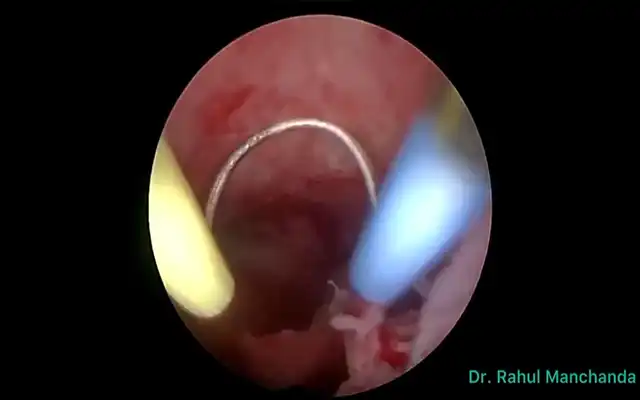

Fig 5: Second Look laparoscopy: White arrow subtle thin adhesions after major posterior myomectomy after the use of barriers (Sprayshield). Blue arrows: impressions of the ischemic sutures at laparoscopic myomectomy using Vicryl 1 resorbable suture. (ZNA series second look)